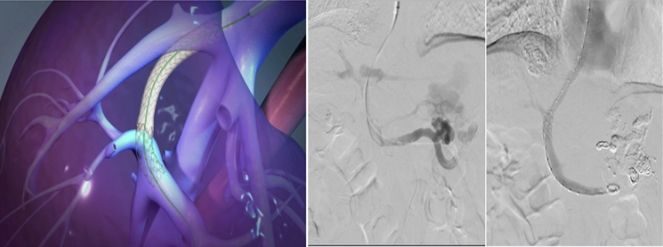

术中,刘一强快速精准采用一“堵”一“疏”的介入手术。1小时内完成止血,术后病情稳定,于第二天转回普通病房。

一“堵”:经皮肝穿食管胃底静脉栓塞, 快速止血稳定患者生命体征

一“疏”:经颈静脉肝内门体分流术(TIPS)或 经肠系膜上静脉肝外门体分流术(TEPS),建立人工分流道从根本上解决门静脉高压,为患者搭建生命通道!

杜大哥的症状更适合TIPS,对于合并门静脉海绵样变和门静脉系统多发血栓的患者,可以采用TEPS技术。